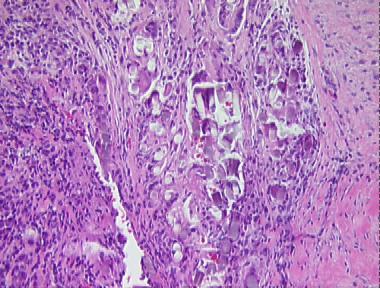

suture granuloma

Histologic Features